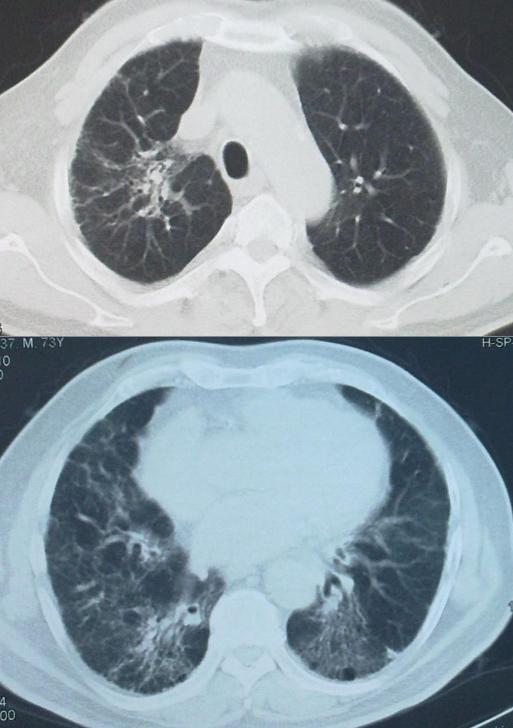

胸部CT:不规则索条影、网格、结节(小叶中心)、磨玻璃;肺结构改变更明显,支气管扩张,蜂窝肺;肺皱缩(上叶)下叶代偿性肺气肿,但是无钙化和空洞;马赛克(主要见于亚急性/慢性);支气管血管束增重。

这是一位73岁男性的胸部CT,1991年始咳嗽,CT诊断ILD。激素治疗减轻,2008年活动气短。养鸽子10年×90只,2000年脱离,吸烟3年×2-3支/天,戒烟48年。胸膜下肺 底 分布不是其特点。